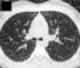

Bronchial wall thickening